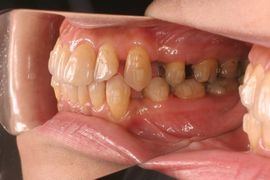

治療開始から4ヶ月後、8個目のアライナーが終了した時の口腔内写真とクリンチェック(シミュレーション)の比較です。

ここまでの経過はとても良好。食事と歯磨き以外は終日装着している状況で1日の平均装着時間は20時間を超えています。抜歯症例であってもしっかりとクリンチェック通りに歯が動いていますね(クリンチェック上の抜歯部位にはまだ仮歯が描かれていますが実際の口腔内にはありません)。

4ヵ月後口腔内右側面

4ヵ月後クリンチェック右側面

初診時口腔内右側面